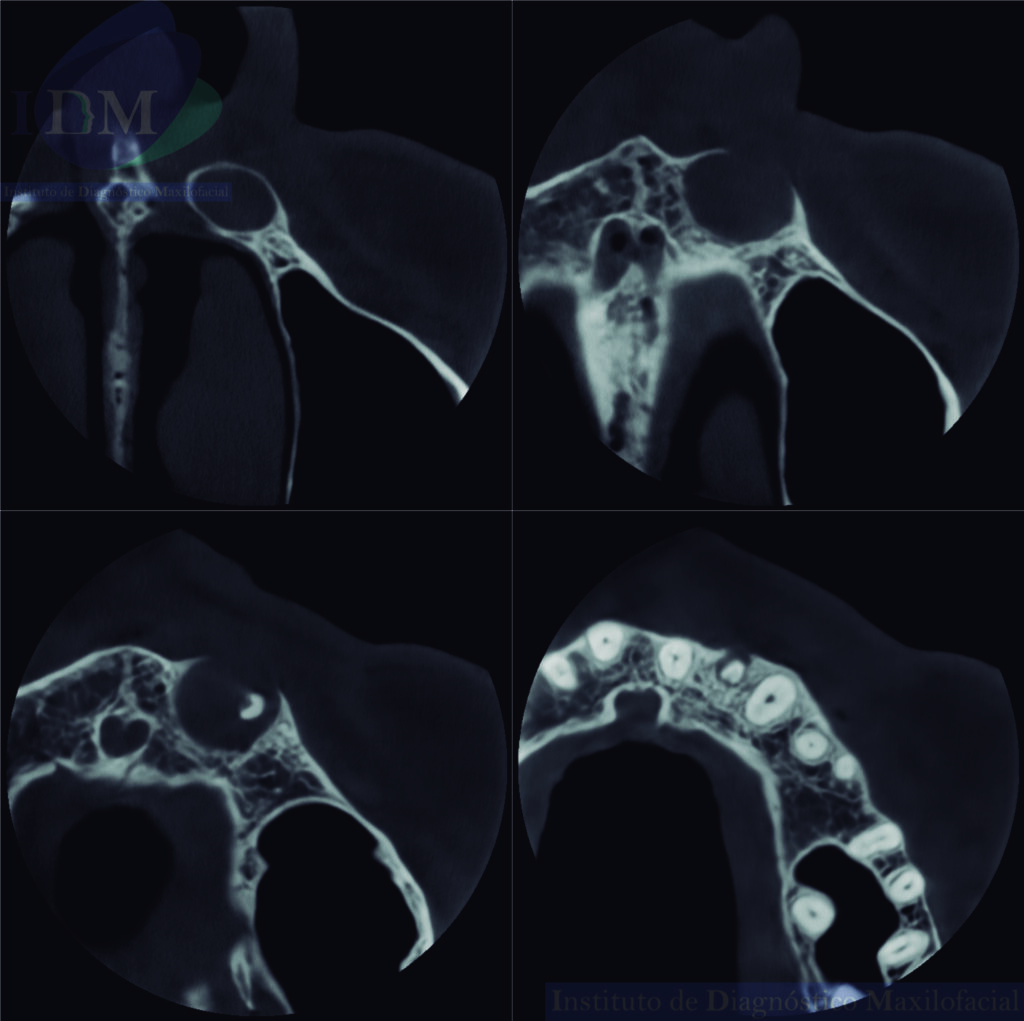

A la evaluación de la tomografía volumétrica (CBCT) en los cortes axiales (Figura 2) y transaxiales (Figura 3), se aprecia imagen isodensa unilocular que se extiende en sentido cefálico caudal desde piso de fosa nasal izquierda hasta tercio apical de piezas 22 y 23, en sentido mesio distal desde distal de pieza 21 hasta mesial de pieza 24, que ocasiona borramiento parcial de la lámina dura de piezas 22 y 23, adelgazamiento del piso de fosa nasal izquierda; adelgazamiento, expansión y erosión parcial de la tabla ósea vestibular.

CORTES AXIALES